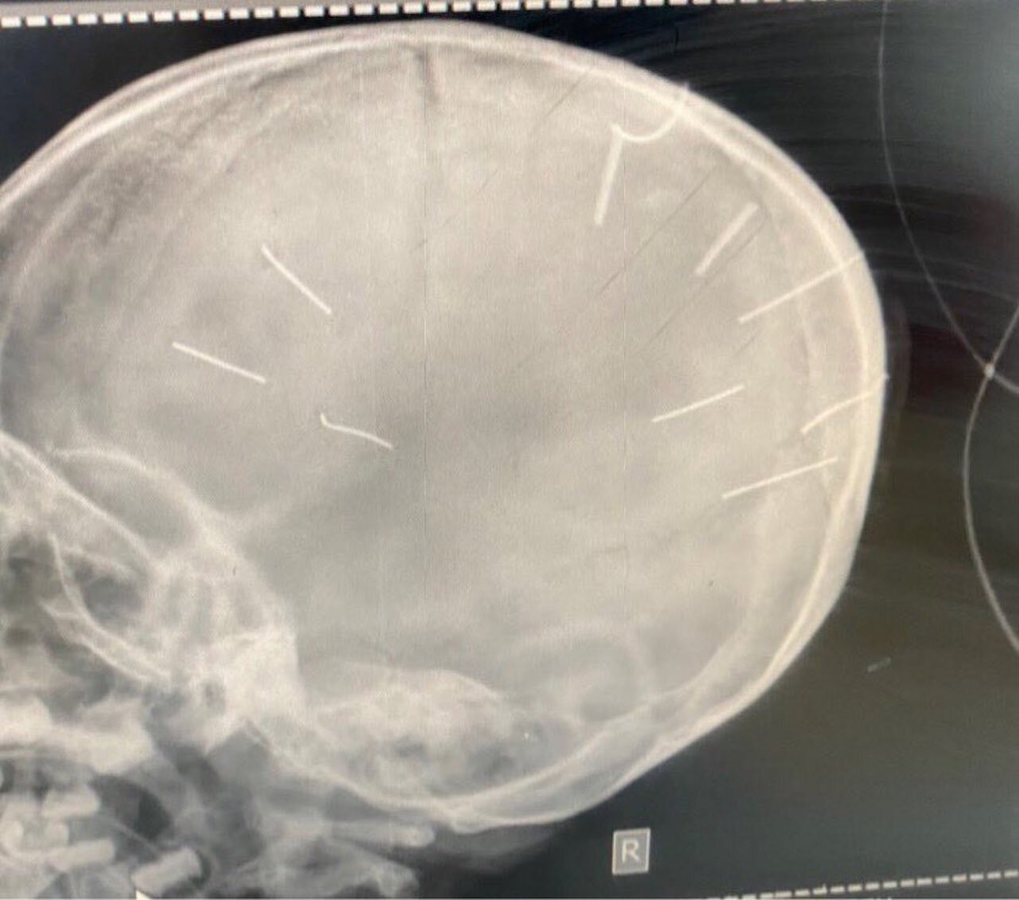

Hình ảnh chụp Xquang hộp sọ bệnh nhi

Bệnh nhi được đặt ống, chụp phim chẩn đoán. Kết quả hộp sọ bệnh nhi có hình ảnh cản quang. Bệnh nhi được chẩn đoán sơ bộ hôn mê nghi viêm màng não.

Đáng chú ý, tại Bệnh viện Đa khoa Xanh Pôn, kết quả phim chụp cắt lớp cho thấy bệnh nhi Đ.N.A. có hình ảnh như bị đinh bắn vào sọ. “Có 9 chiếc đinh. Bệnh nhân đang trong tình trạng rất nặng, đe doạ tử vong cao”, BS Kiên cho biết thêm.